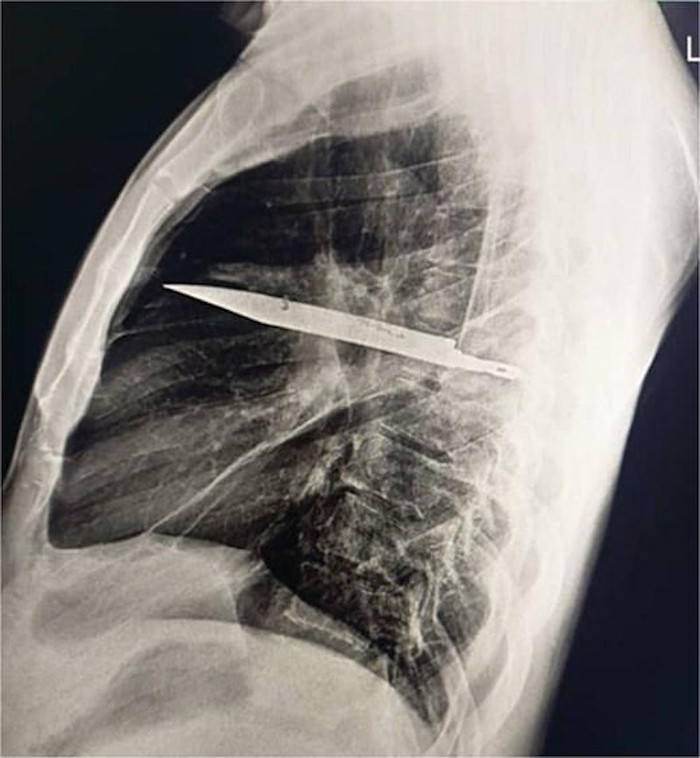

Trong quá trình thăm khám, người đàn ông nhớ lại một biến cố trong quá khứ: tám năm trước, anh từng tham gia một cuộc ẩu đả dữ dội, bị chém nhiều nhát vào mặt, lưng, ngực và bụng. Dù đã được điều trị, nhưng dường như có điều gì đó bị bỏ sót. Các bác sĩ quyết định chụp X-quang, và phát hiện sự thật gây sốc: một lưỡi dao lớn vẫn còn găm trong lồng ngực anh suốt tám năm qua.

Kết quả hình ảnh cho thấy lưỡi dao xuyên qua xương bả vai phải và nằm trong khoang ngực, nhưng may mắn không đụng chạm đến tim, phổi hay các cơ quan trọng yếu khác. Chính sự “ăn may” này đã giúp bệnh nhân sống sót mà không gặp biến chứng nghiêm trọng trong suốt thời gian dài. Chỉ đến khi cơ thể phản ứng bằng việc rỉ mủ từ vùng ngực, bí mật khủng khiếp mới được phơi bày.